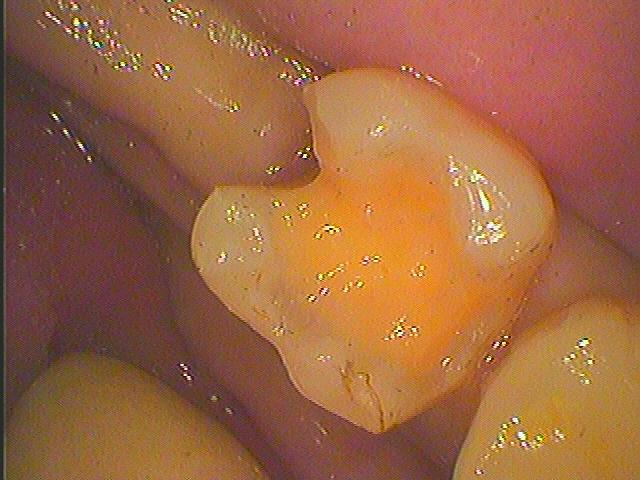

同じ方の左下7番になります

銀歯を外していきました

左下の7番